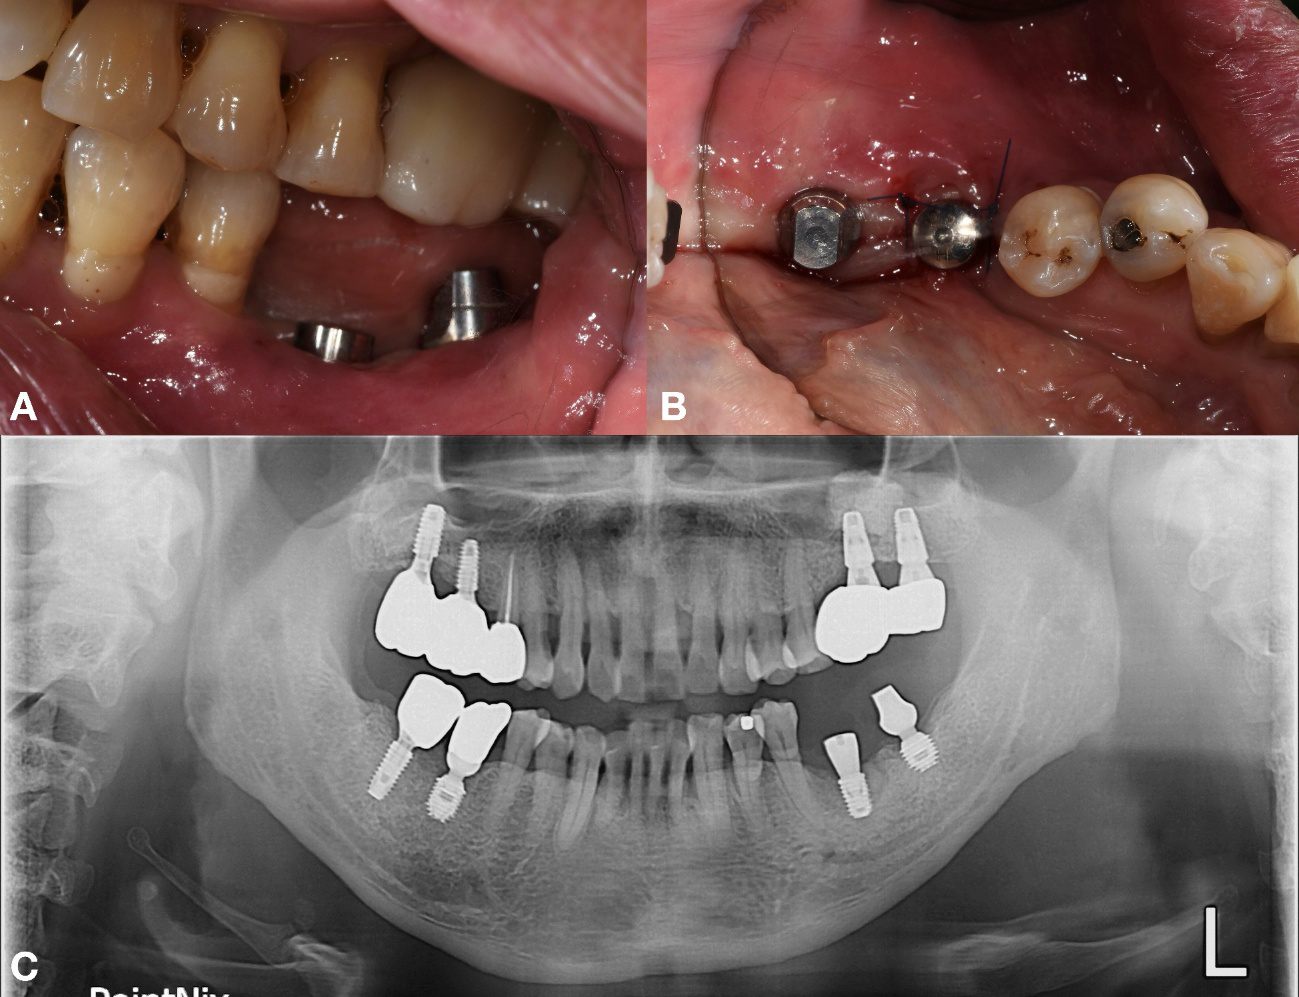

No documentation regarding the implants was available; therefore, the KAOMI implant finder service was consulted. The system identified the type of fixtures as Bicon implants (Bicon LLC; Boston, MA, USA). Based on this information, the manufacturer was contacted, and an appropriate abutment for #37 the fixture, intended for salvage, was procured (Fig. 2).

The procedure progressed uneventfully. The failing implant at site #36 was removed, followed by guided bone regeneration (GBR). The extraction socket was grafted with freeze-dried bone allograft (FDBA) (Sure-OssTM-POWDER; HansBioMed, Seoul, Korea), covered with a self-expanding biodegradable collagen matrix (Regenomer; NIBEC, Chungbuk, Korea), and sutured with 4-0 nylon (Blue nylon; Ailee Co, Busan, Korea).

After a healing period of approximately 5 months, a new implant (TSIII, 4.5 mm diameter, 7 mm length; Osstem Implant, Busan, Republic of Korea) was placed at site #36 with an initial torque of 25 Ncm. A healing abutment (95 mm diameter, 7 mm height) was placed simultaneously (Fig. 3).

Approximately 3 months after implant placement of #36 implant, prosthetic rehabilitation was initiated. A custom abutment was fabricated for #36, and a new abutment was delivered for the salvaged, preexisting fixture of implant #37 (Figs. 4 and 5).